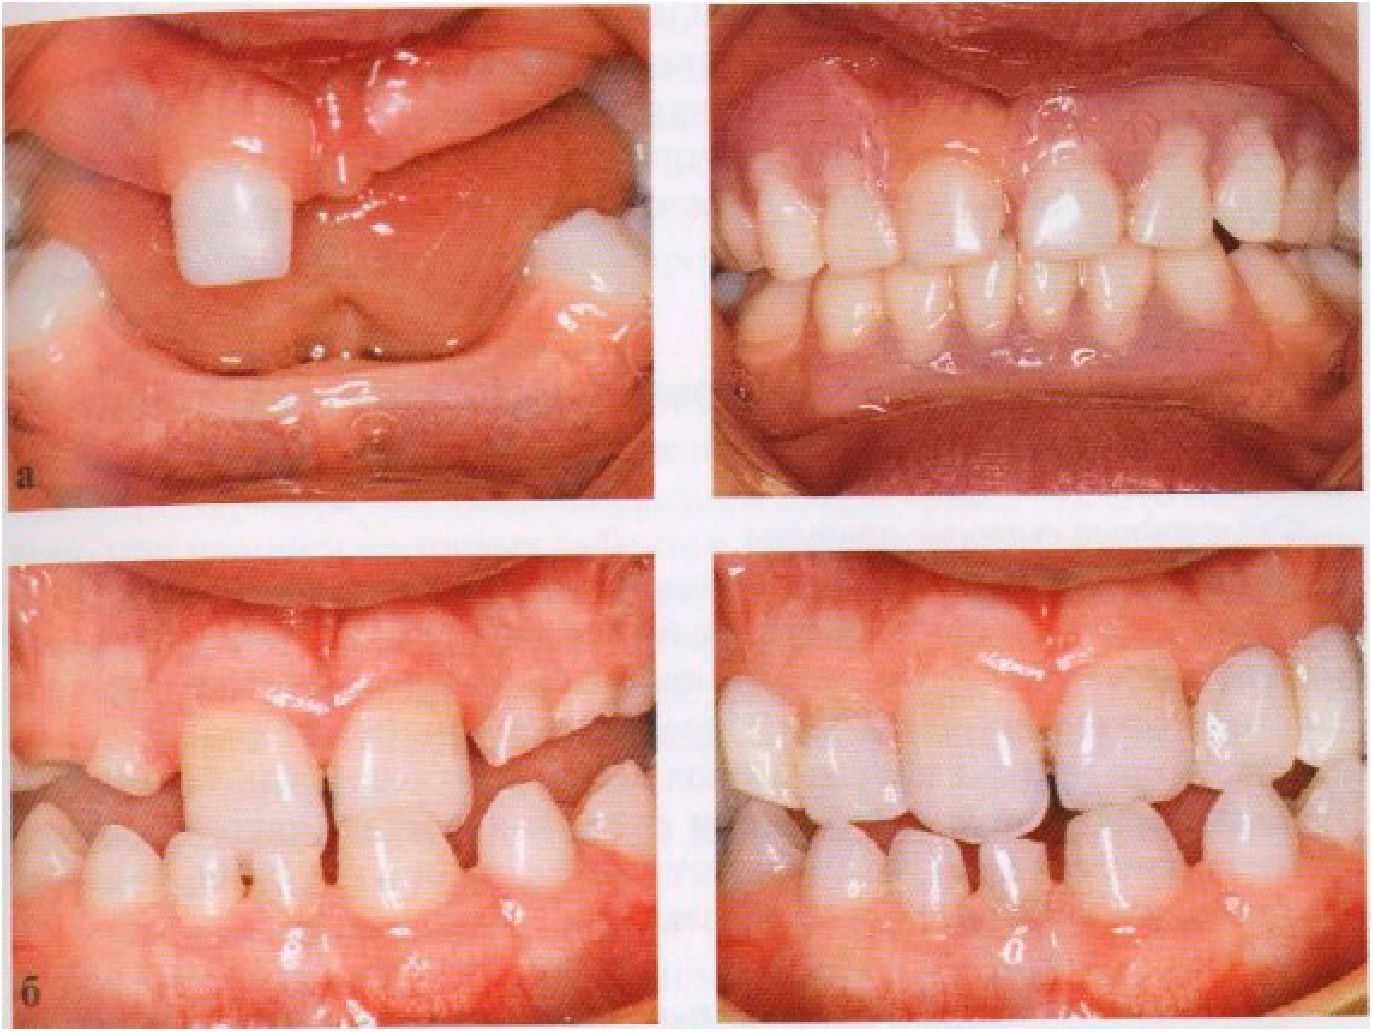

Рис. 7-7. (а, б) Примеры применения временных частичных съемных протезов у детей со значительной гиподентией.

Когда планируется постоянное замещение адентии (врожденного отсутствия зачатков зубов. — Пргшеч. ред.) путем протезирования с использованием имплантатов, этот план не реализуется до тех пор, пока не завершится период роста. В течение этого времени по эстетическим и функциональным показаниям применяются временные частичные съемные протезы. Это обычно имеет место у пациентов со значительной гиподентией. У них применение обычных съемных протезов, опирающихся на слизистую оболочку, а также перекрывающих имеющиеся зубы и восстанавливающих окклюзионную высоту лица, вызывает значительное улучшение внешнего вида и функций жевания и речи (рис. 7-7).

Подобные протезы также могут применяться в качестве ретенционных аппаратов после завершения активного периода ортодонтического лечения. С учетом происходящего роста челюстей и прорезывания зубов, съемный протез обычно делается из акриловой пластмассы, что позволяет его легкую подгонку и реконструкцию. И это предпринимается несмотря на возможность поломки и потери съемного протеза. В большинстве случаев достаточное улучшение внешнего вида и функций жевания и речи может быть достигнуто путем создания только протеза верхней челюсти. Это облегчает применение конструкции, которая, улучшая внешний вид пациента, исключает нежелательные повреждения мягких тканей.